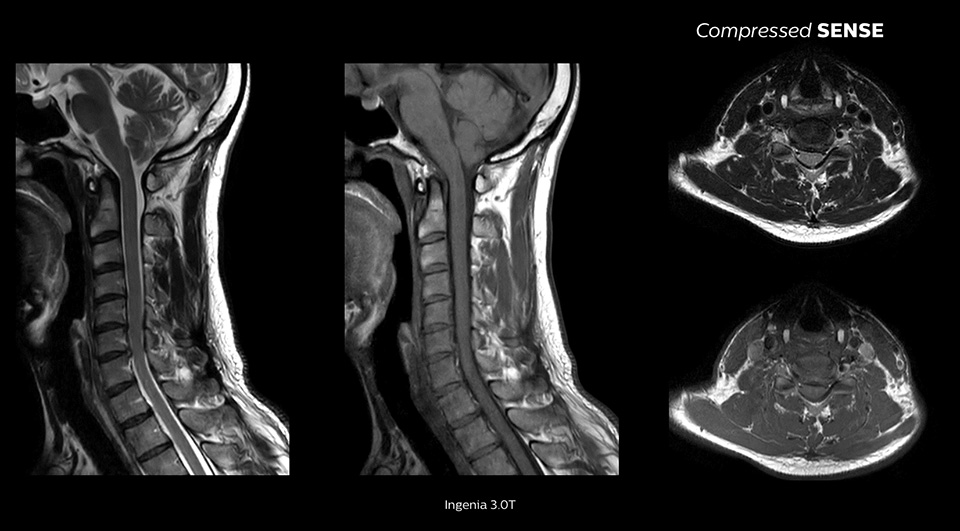

Bei nahezu unverminderter Bildqualität1

Wir führen im Prinzip unsere standardmäßigen Protokolle aus und aktivieren nur Compressed SENSE und erreichen eine 20 % kürzere Scandauer. Keiner der Ärzte merkt bei der Befundung, ob es sich um einen Scan mit oder ohne Compressed SENSE handelt.“

John P. Karis, M.D., Leiter MRT und Brain-Imaging, Abteilung für Neuroradiologe am Barrow Neurological Institute, USA

Mögliche Verbesserung der räumlichen Auflösung um bis zu 64 %1